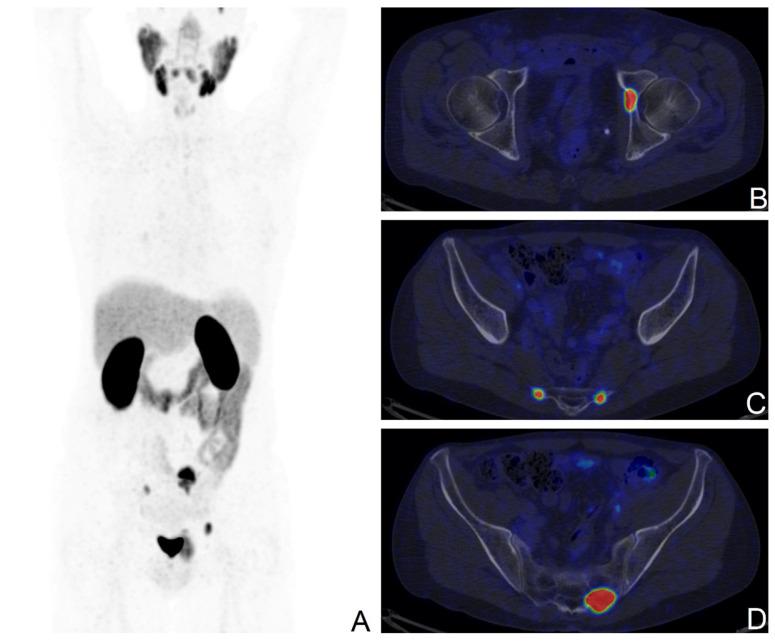

Localized prostate cancer (PCa) can be treated with radical prostatectomy (RP). Up to 30% of patients undergoing this procedure experience biochemical recurrence (BCR), namely the rise in serum prostate-specific antigen (PSA) levels during the post-surgical follow-up, requiring further treatments and with the risk of severe disease progression. Currently, the most accurate imaging technique to confirm, detect, and locate disease relapses in BCR patients is prostate-specific membrane antigen (PSMA)-targeted PET, as recommended by international clinical guidelines. The aim of the study was to investigate potential clinical and pathological predictors of PSMA PET positivity, validated by clinical and instrumental follow-up or histopathological data. In this study, a selected cohort of BCR patients after RP and no other PCa-related therapy who underwent either PSMA PET/CT or PSMA PET/MRI has been analysed. Among the considered predictors, both pathological staging after RP equal or higher than pT3a and higher PSA levels at the time of the scan were significantly correlated with PSMA PET positivity on multivariate logistic regression analysis. As expected, PSMA PET confirmed its role as an accurate imaging technique in the setting of BCR in PCa. These findings may inform appropriate and tailored patient selection and scan timing to optimize and fully exploit this powerful diagnostic tool.

局限性前列腺癌(PCa)可通过根治性前列腺切除术(RP)进行治疗。接受该手术的患者中,高达30%会出现生化复发(BCR),即在术后随访期间血清前列腺特异性抗原(PSA)水平升高,这需要进一步治疗且存在疾病严重进展的风险。目前,国际临床指南推荐,对于BCR患者,确认、检测和定位疾病复发的最准确成像技术是前列腺特异性膜抗原(PSMA)靶向PET。本研究的目的是通过临床和仪器随访或组织病理学数据验证,调查PSMA PET阳性的潜在临床和病理预测因素。在本研究中,分析了一组经过筛选的RP术后且未接受其他PCa相关治疗、接受了PSMA PET/CT或PSMA PET/MRI检查的BCR患者。在考虑的预测因素中,RP术后病理分期等于或高于pT3a以及扫描时较高的PSA水平在多因素逻辑回归分析中均与PSMA PET阳性显著相关。正如预期的那样,PSMA PET证实了其在PCa的BCR情况下作为一种准确成像技术的作用。这些发现可能为适当且个性化的患者选择和扫描时机提供参考,以优化并充分利用这一强大的诊断工具。